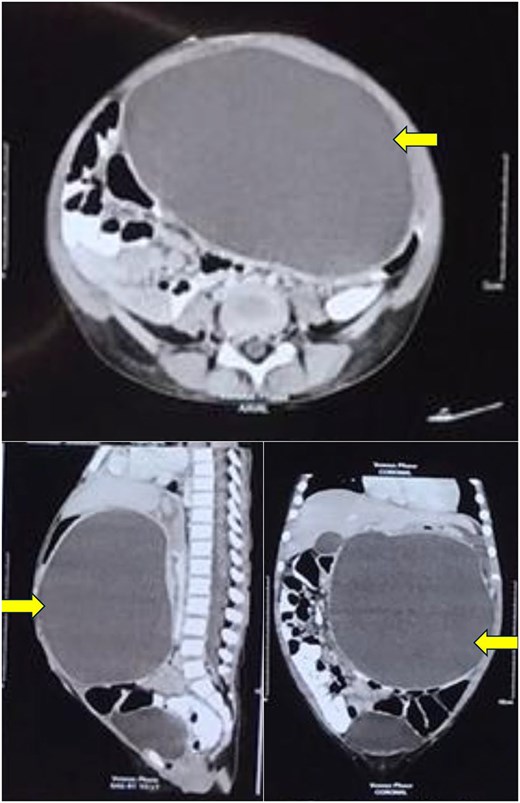

Computerized tomography of the abdomen showing a large thin-walled cystic hypodense lesion (arrow), anterior to the pancreas and compressing it, anteriorly displacing the stomach and compressing it, and abutting the anterior abdominal wall in axial, sagittal, and coronal views.

A 4-year-old girl presented in September 2020 with abdominal distention for 1 month and abdominal pain for 20 days. The onset of abdominal pain was associated with repeated episodes of vomiting on a single day. There was no history of abdominal trauma or similar complaints in the past. On examination, an everted umbilicus and distended veins over the abdomen were visualized. The abdomen was tense, distended and a fluid thrill was palpable. Other general and systemic examinations were normal. Serum amylase was 1964 IU/L (normal: 40–140 IU/L). Other investigations of the patient are shown in Table 1. Abdominal ultrasound done prior to presentation in August 2020 showed a well-defined cystic mass in the left lumbar region measuring 10.6 × 12.6 × 12.9 cm (volume: 916 cc) with no septations or solid components within. The wall thickness of the cyst was 6 mm. Contrast-enhanced computerized tomography (CECT) of the abdomen showed a large thin-walled cystic hypodense lesion measuring 13 × 10.2 × 17 cm, anterior to the pancreas and compressing and anteriorly displacing the stomach, suggestive of a pancreatic pseudocyst or GDC. The maximum wall thickness was 2.3 mm and there were no calcifications, septations, or solid components within the cyst (Fig. 1). Endoscopic ultrasound (EUS) showed a large well-defined fluid collection measuring ˃17 cm replacing the entire pancreas, suggestive of a pancreatic pseudocyst. EUS-guided cystogastrostomy was done in which ⁓1.5 L of cyst fluid was aspirated and a double pigtail stent was inserted into the cyst. Post-procedure abdominal ultrasound showed a residual cyst in the epigastric regionmeasuring 9 × 9.5 × 7.5 cm (volume: 360 cc) with the drain in-situ. Post-stenting MRCP confirmed a residual thick-walled cystic lesion with air-fluid levels, anterior to the pancreas and posteroinferior to the stomach, with an inner mucosal lining suggestive of a GDC (Fig. 2). The pancreas appeared normal. She underwent surgical excision which confirmed the diagnosis of a GDC and was doing well on follow-up.